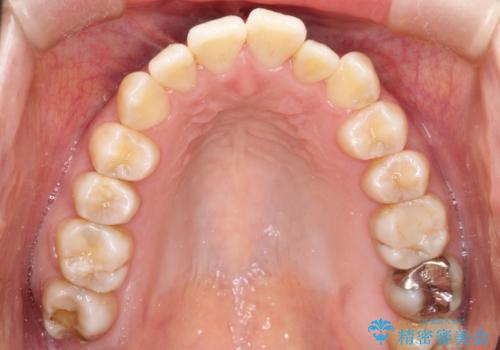

- 前歯のガタガタと、かみ合わせを改善したいとのことで来院されました。

人前でお話をするお仕事のため、装置をつけないでよいマウスピース矯正を希望されました。

下顎の歯が、上顎の歯に対して前方に位置していたので、下顎の歯を後方に移動させるのと、歯と歯の間を削りスペースを作り、歯を並べる計画としました。